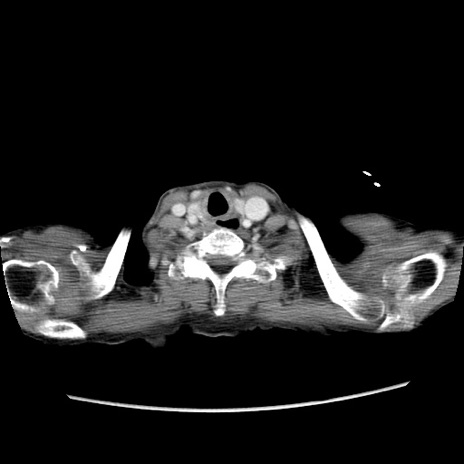

症例25(横断像)

【症例】80歳代女性

【主訴】胸のつかえ感

【現病歴】約9時間前に食後から胸のつかえた感じあり、嘔吐あり、来院。

【既往歴】胃癌(全摘)、胆摘、虫垂炎

【身体所見】心窩部に圧痛あり、反跳痛なし。

【データ】WBC 5700、CRP 0.05